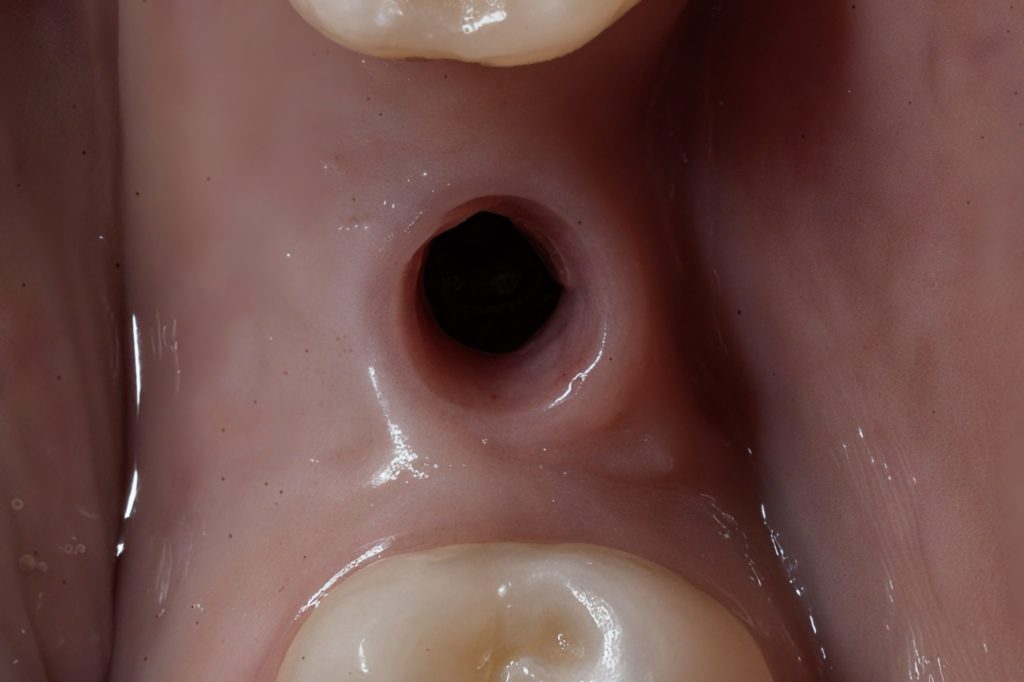

2. Abutment Connection

A precision-milled titanium base abutment was torqued to the manufacturer’s specification. The abutment contour was selected to promote a natural gingival transition and preserve the mucosal seal.

2️⃣ Abutment connection and soft-tissue support